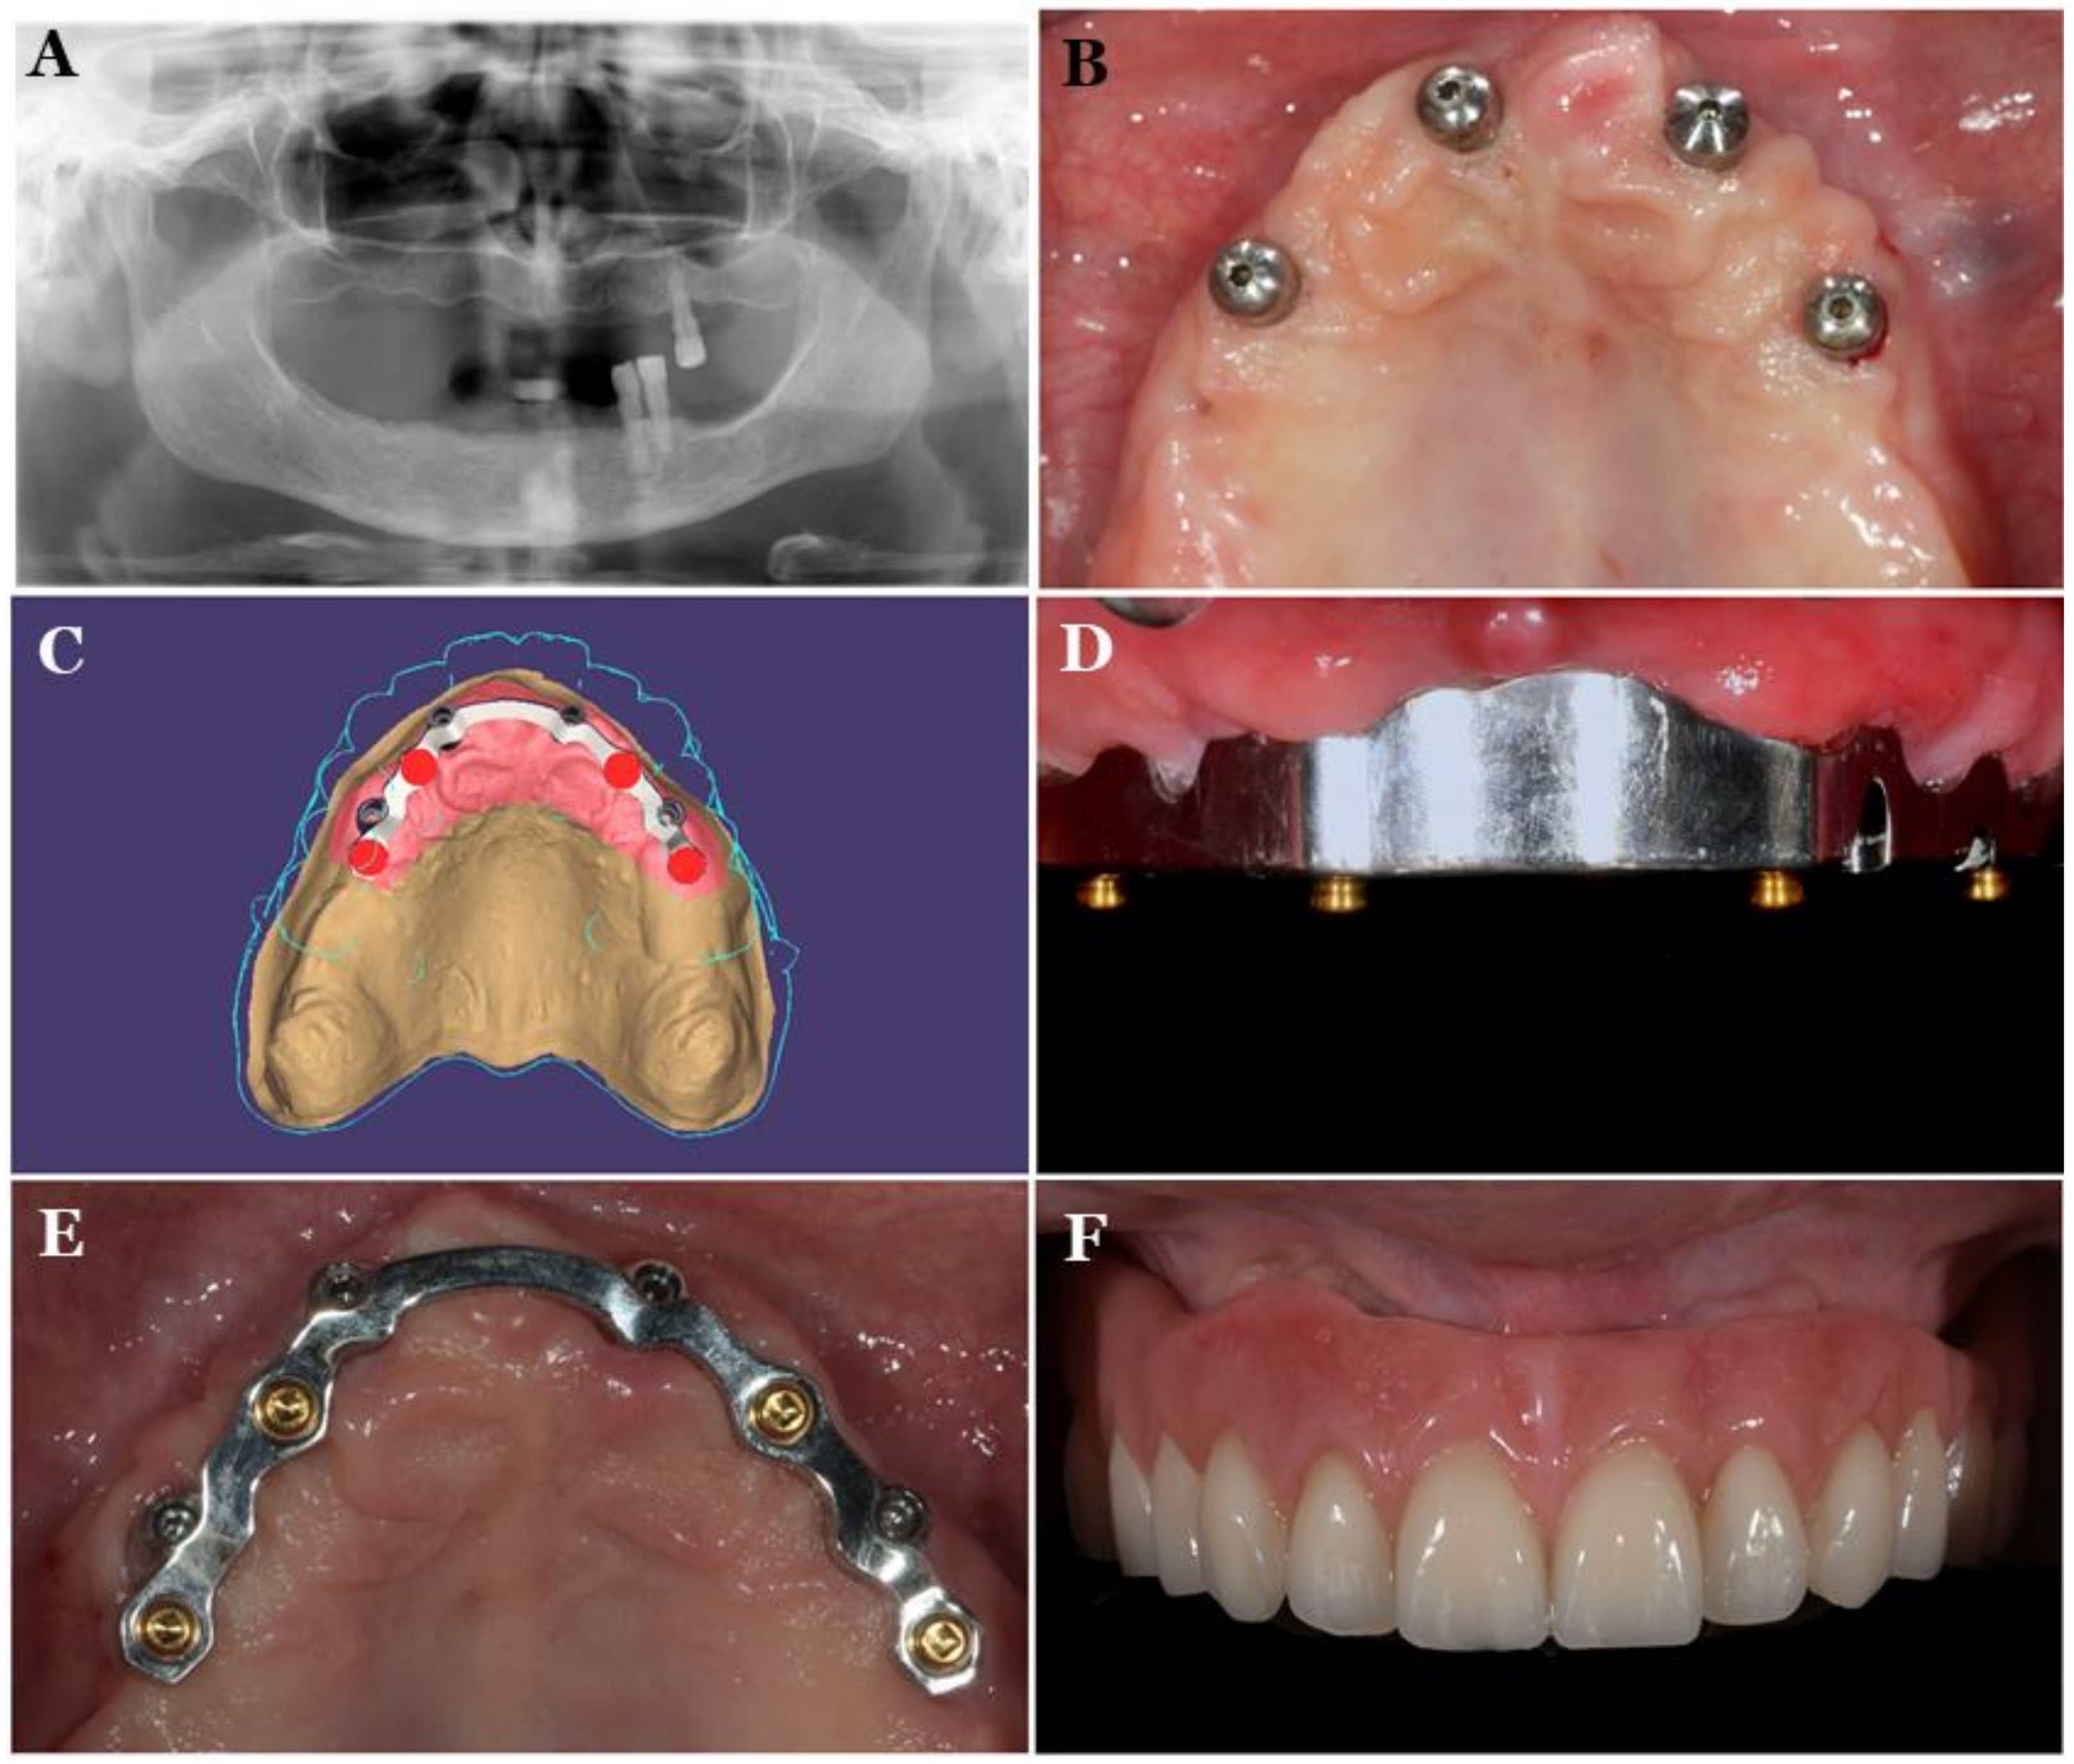

- Tallarico, M.; Cervino, G.; Scrascia, R.; Uccioli, U.; Lumbau, A.; Meloni, S.M. Minimally invasive treatment of edentulous maxillae with overdenture fully supported by a cad/cam titanium bar with a low-profile attachment screwed on four or six implants: A case series. Prosthesis 2020, 2, 53–64. [Google Scholar] [CrossRef]